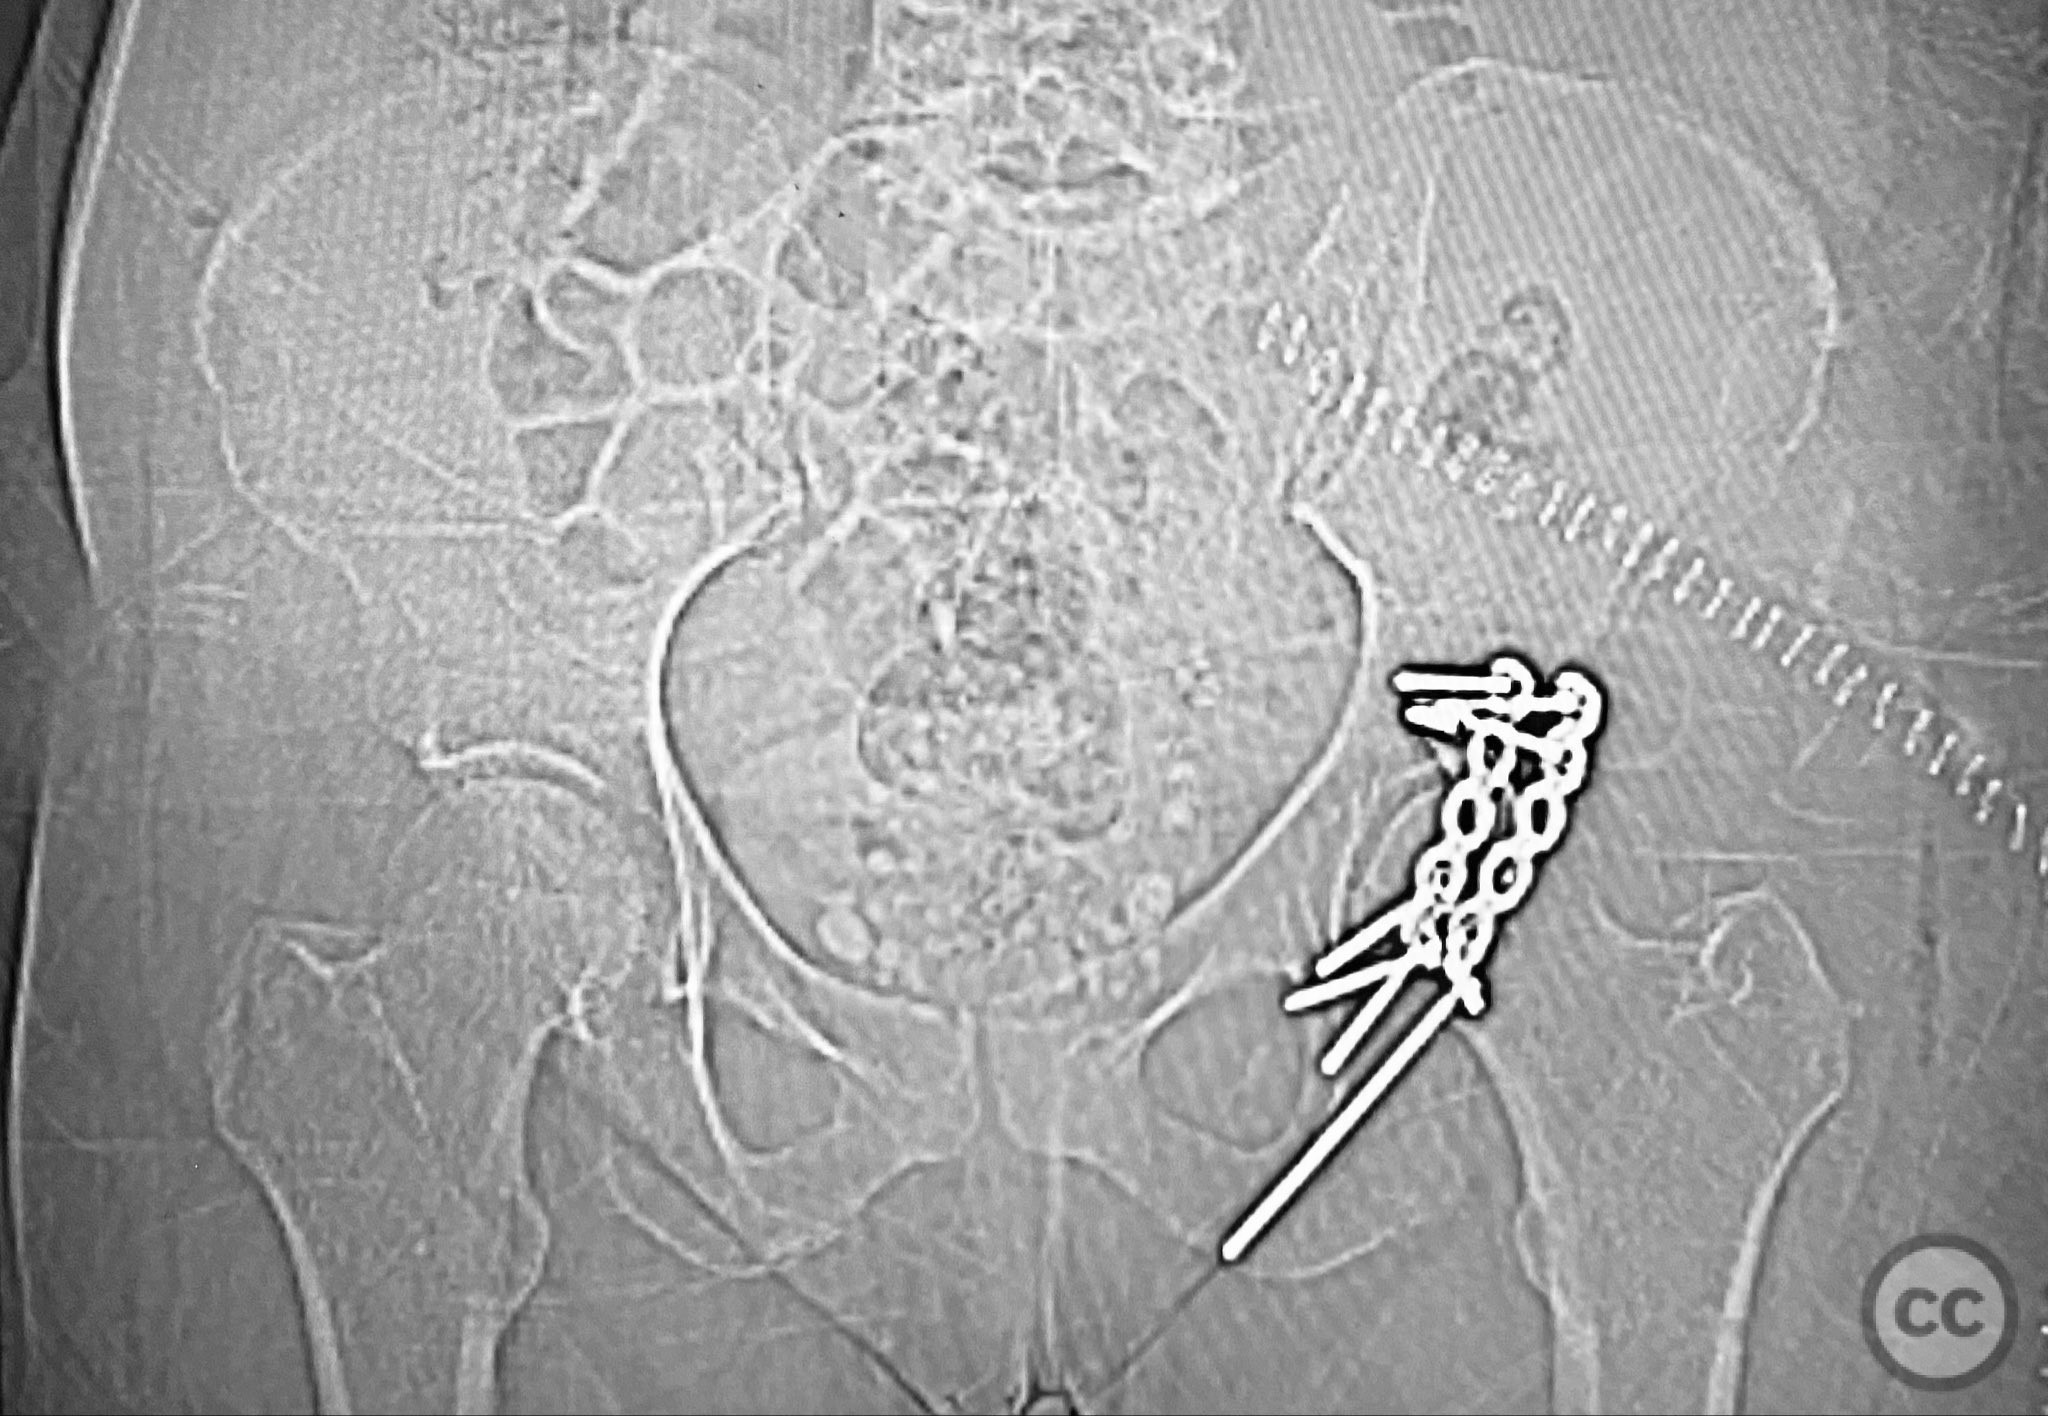

Clinical and radiological findings:  A patient sustained a posterior wall acetabular fracture-dislocation, characterized by comminution of the posterior wall, impaction of fragments into the posterior column region, and intra-articular loose fragments within the fossa acetabuli. Sagittal imaging demonstrated femoral head impalement on the intact wall, raising concern for potential irreducibility. Coronal and axial CT images revealed acetabular and femoral head impactions, peripheral wall comminution, incomplete fracture extension at the acetabular notch and quadrilateral surface, and an articular fragment within the joint. Surface renderings confirmed the extent of peripheral wall comminution and impaction. Despite these findings, a closed manipulative reduction was successfully achieved, resulting in a congruent reduction on post-reduction imaging.

Planning remarks:  The preoperative plan included a prone Kocher-Langenbeck (KL) approach to the acetabulum. The plan involved application of a distractor to facilitate removal of intra-articular loose fragments, elevation of impacted articular segments, bone grafting of resultant defects with ground allograft, and stabilization of the posterior wall with multiple plates, including a custom spring hook plate for peripheral fragment support.

The injury demonstrated extensive comminution and impaction of the posterior wall with intra-articular debris requiring meticulous removal and elevation. The use of a distractor facilitated both exposure and removal of loose articular fragments. The peripheral comminution necessitated augmentation with a custom spring hook plate to maintain reduction of small cortical fragments not amenable to standard buttress plating. Proper placement of the lateral reconstruction plate overlying the spring hook plate was critical for maintaining fixation integrity; malpositioning resulted in early fixation failure in a comparative case due to bending of the unsupported spring hook implant.